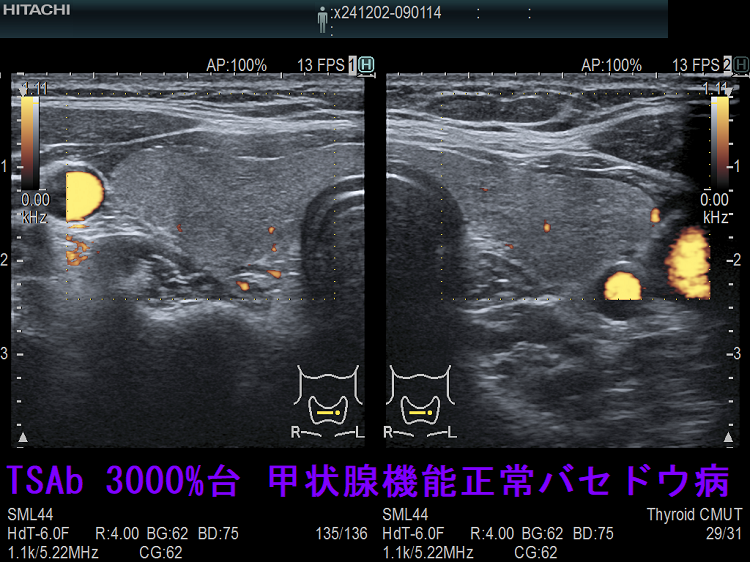

TSAb 3000%台 甲状腺機能正常バセドウ病;この状態が3年以上続いており、TSBAb(TSHレセプター抗体[阻害型]、甲状腺刺激阻害抗体)が拮抗している可能性を考えます。

TSAb 3000%台 甲状腺機能正常バセドウ病 下甲状腺動脈血流速度(ITA-PSV)は正常